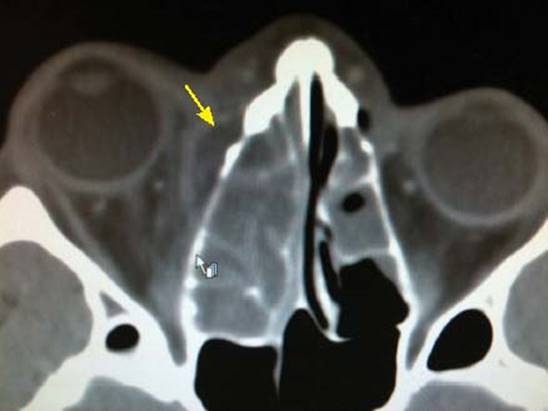

Ключевую роль играют именно инструментальные исследования. Наиболее распространенным и доступным методом является рентгенография носовых пазух. Для выявления не только воспалительного процесса, но и возможных осложнений используется компьютерная томография.

Точный диагноз может установить только врач-отоларинголог. Для этого он направит пациента на комплексное обследование, которое включает общие анализы, осмотр, рентген и томографию. Успех лечения во многом зависит от правильно проведенной диагностики.